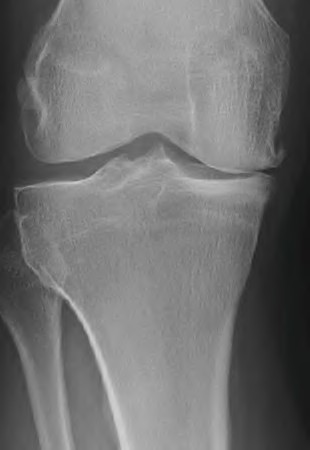

A 55-year-old male presents with isolated medial compartment osteoarthritis of the right knee. He is being evaluated for a medial unicompartmental knee arthroplasty (UKA). Which of the following physical examination or radiographic findings is an absolute contraindication to a medial UKA?